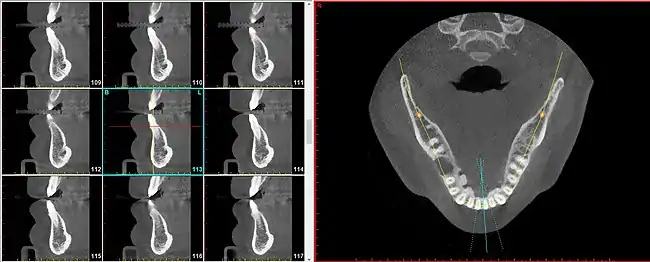

The radial plane can be useful because certain anatomical elements repeat in a circumferential manner (such as around the curvature of the dental arch (i.e. the jaw) and to speak of these entities using parallel planes becomes cumbersome and inaccurate.

For instance, the segment of bone on the outer circumference of each individual tooth is referred to as the facial plate of bone. Because the facial plate of bone is anterior to the incisors (in the front of the mouth) but lateral to the premolars and molars (in the back of the mouth), to visualize the facial plate of bone on various teeth will require sagittal slices for the former but coronal slices for the latter. To achieve greater uniformity and diminished confusion, simply speaking of radial slices provides a satisfactory solution for all teeth in both (upper and lower) arches.